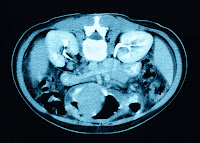

| an image of kidneys from an MRI |

The ultrasound checks the health of the kidneys, but a more detailed test must follow. This is the MRI or magnetic resonance imaging. This will test, in depth, the blood vessels and the kidney.

| An MRI representation |